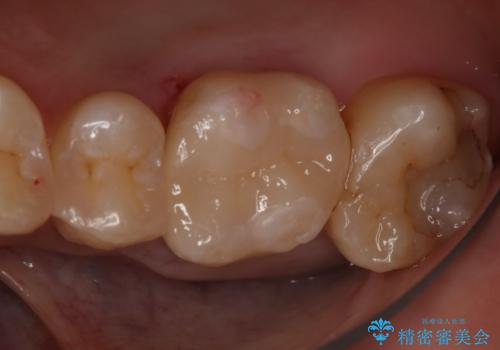

銀の詰め物が取れた セラミックインレー治療

- 右下6番のメタルインレー脱離のため来院。

セラミックの治療を希望されたため切削量を考慮し、セラミックインレーでの治療を選択しました。

う蝕が深くまで進行していたので、CRで裏層した上で形成・印象をしています。